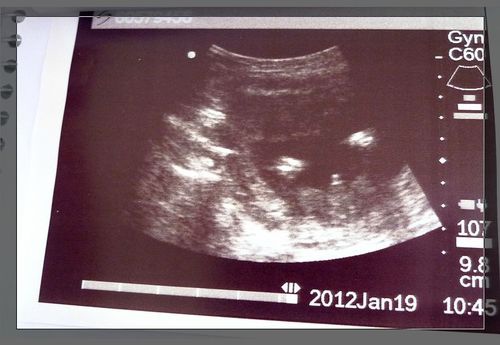

產檢時最令人不清不楚的就是有關於超音波螢幕上所出現的英文縮寫術語